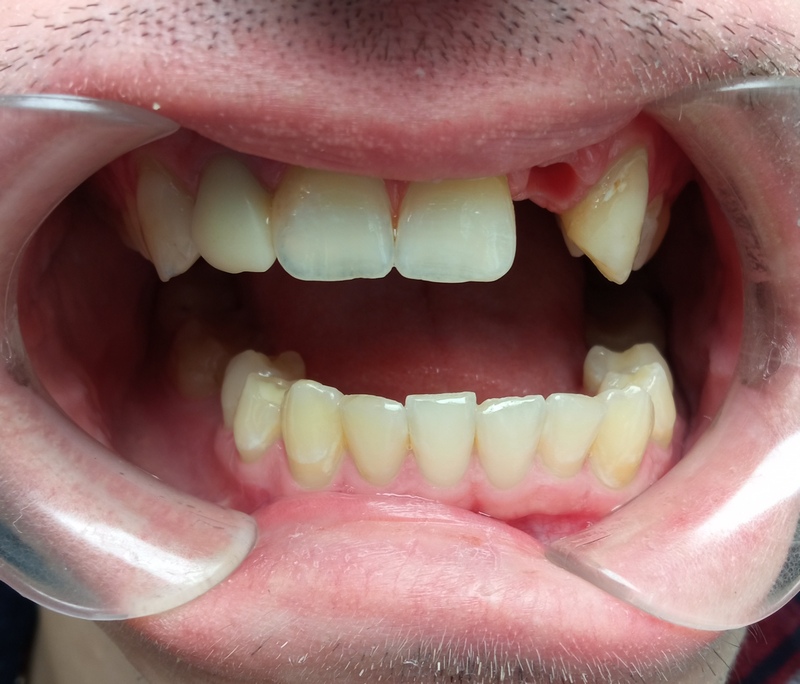

Пример 2

- Провели 3Д КТ обследование 2500 ₽.

- В ходе осмотра состояние полости рта было хорошее, зубы рядом с отсутствующим были сохранены и не поражены кариесом.

- Пациента очень волновало, чтобы зуб не отличался от соседних.

После изучения снимков и учитывая пожелания пациента составили 2 варианта лечения.

2 вариант. Восстановить зуб коронкой на импланте. Срок лечении 7 месяцев.

2 вариант дольше и дороже, но надежнее и навсегда. Во время лечения отсутствующий зуб будет закрыт временной коронкой.

Взвесив все «за» и «против» пациент выбрал вариант 2 – надежность.